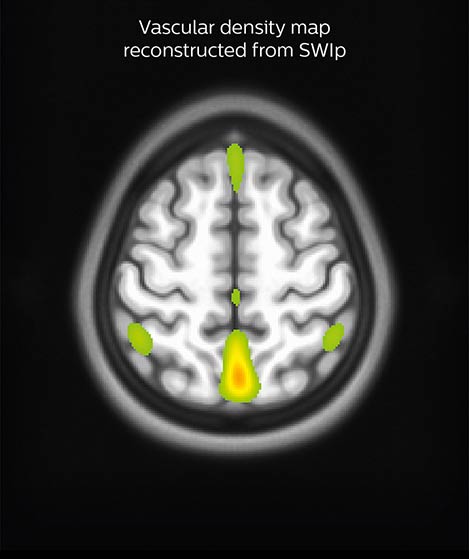

Correcting for vascular density

A SWIp image (left) is used to visualize veins in cortical and sub-cortical areas. Using in-house reconstruction techniques, a vascular density map is obtained in individual subjects and averaged over a population (right). Areas in red/green represent areas with dense venous vascularization. The lab uses such images to correct fMRI (BOLD) activation maps in order to minimize false positives.